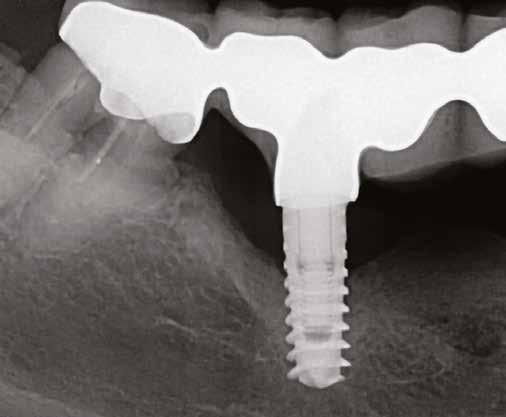

1. ábra: Dr. Jung 10 éves kontrollal rendelkező 4.7-es helyén levő Dentium short implantációja. Preoperativ CT, ínyformázó 4 hónappal a műtét után, valamint 4 hónap múlva 4.7-es szólókorona.

2. ábra: Dr. Park esete. 4.6-os fogon levő jelentős csontfelritkulás röntgenképe, extractio és iGBR alkalmazása Osteon Xenoval. 4 hónap múlva Dentium short implantátum, majd 4 hónap múlva korona készítése.

3. ábra: Dr. Han esete. 2.4-2.5-2.6 lokalizációban keskeny gerinc. Csontpótlás Osteon Xeno- val, majd 4 hónap múlva 3 db Dentium short implantátum behelyezése. 4 hónappal később protetikai munka.

4. ábra: Dr. Chung esete. Short implantátumok 10 éves kontrollja a 4.7 és 1.6-1.7 lokalizációban.

5. ábra: Dr. Chun esete. Dentium Narrow implantátumok és azok protetikai ellátása 4 hónappal a beültetést követően.

6. ábra: Dr. Lim esete. Dentium Narrow implantátumok a felső állcsonton, guide tervezés, ideiglenes hídpótlás azonnali terheléssel, majd 4 hónappal később végleges protetikai ellátás.